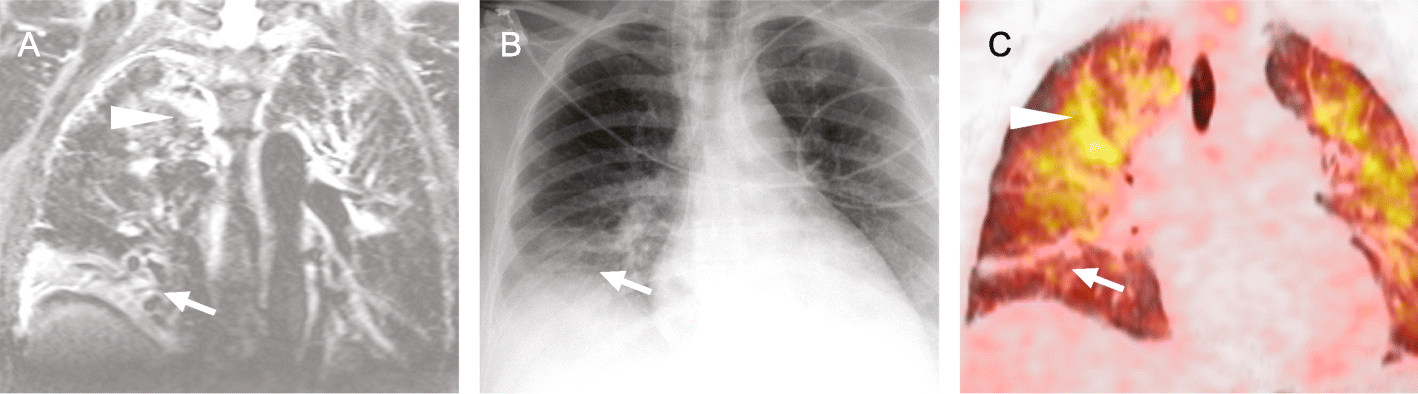

Fig. 4

56-year-old patient with pulmonary infiltrations as infectious focus. Juxtaposition of coronal T2-STIR a, conventional radiography of the chest b and coronal PET-CT c in chronological order. One day elapsed between each image. Note that the middle lobe atelectasis (arrow) resolves over time, while the paramediastinal infiltrations (arrow head) increase. The conventional radiography c shows signs of the atelectasis in the right lower zone but no clear sign of the paramediastinal pulmonary infiltration